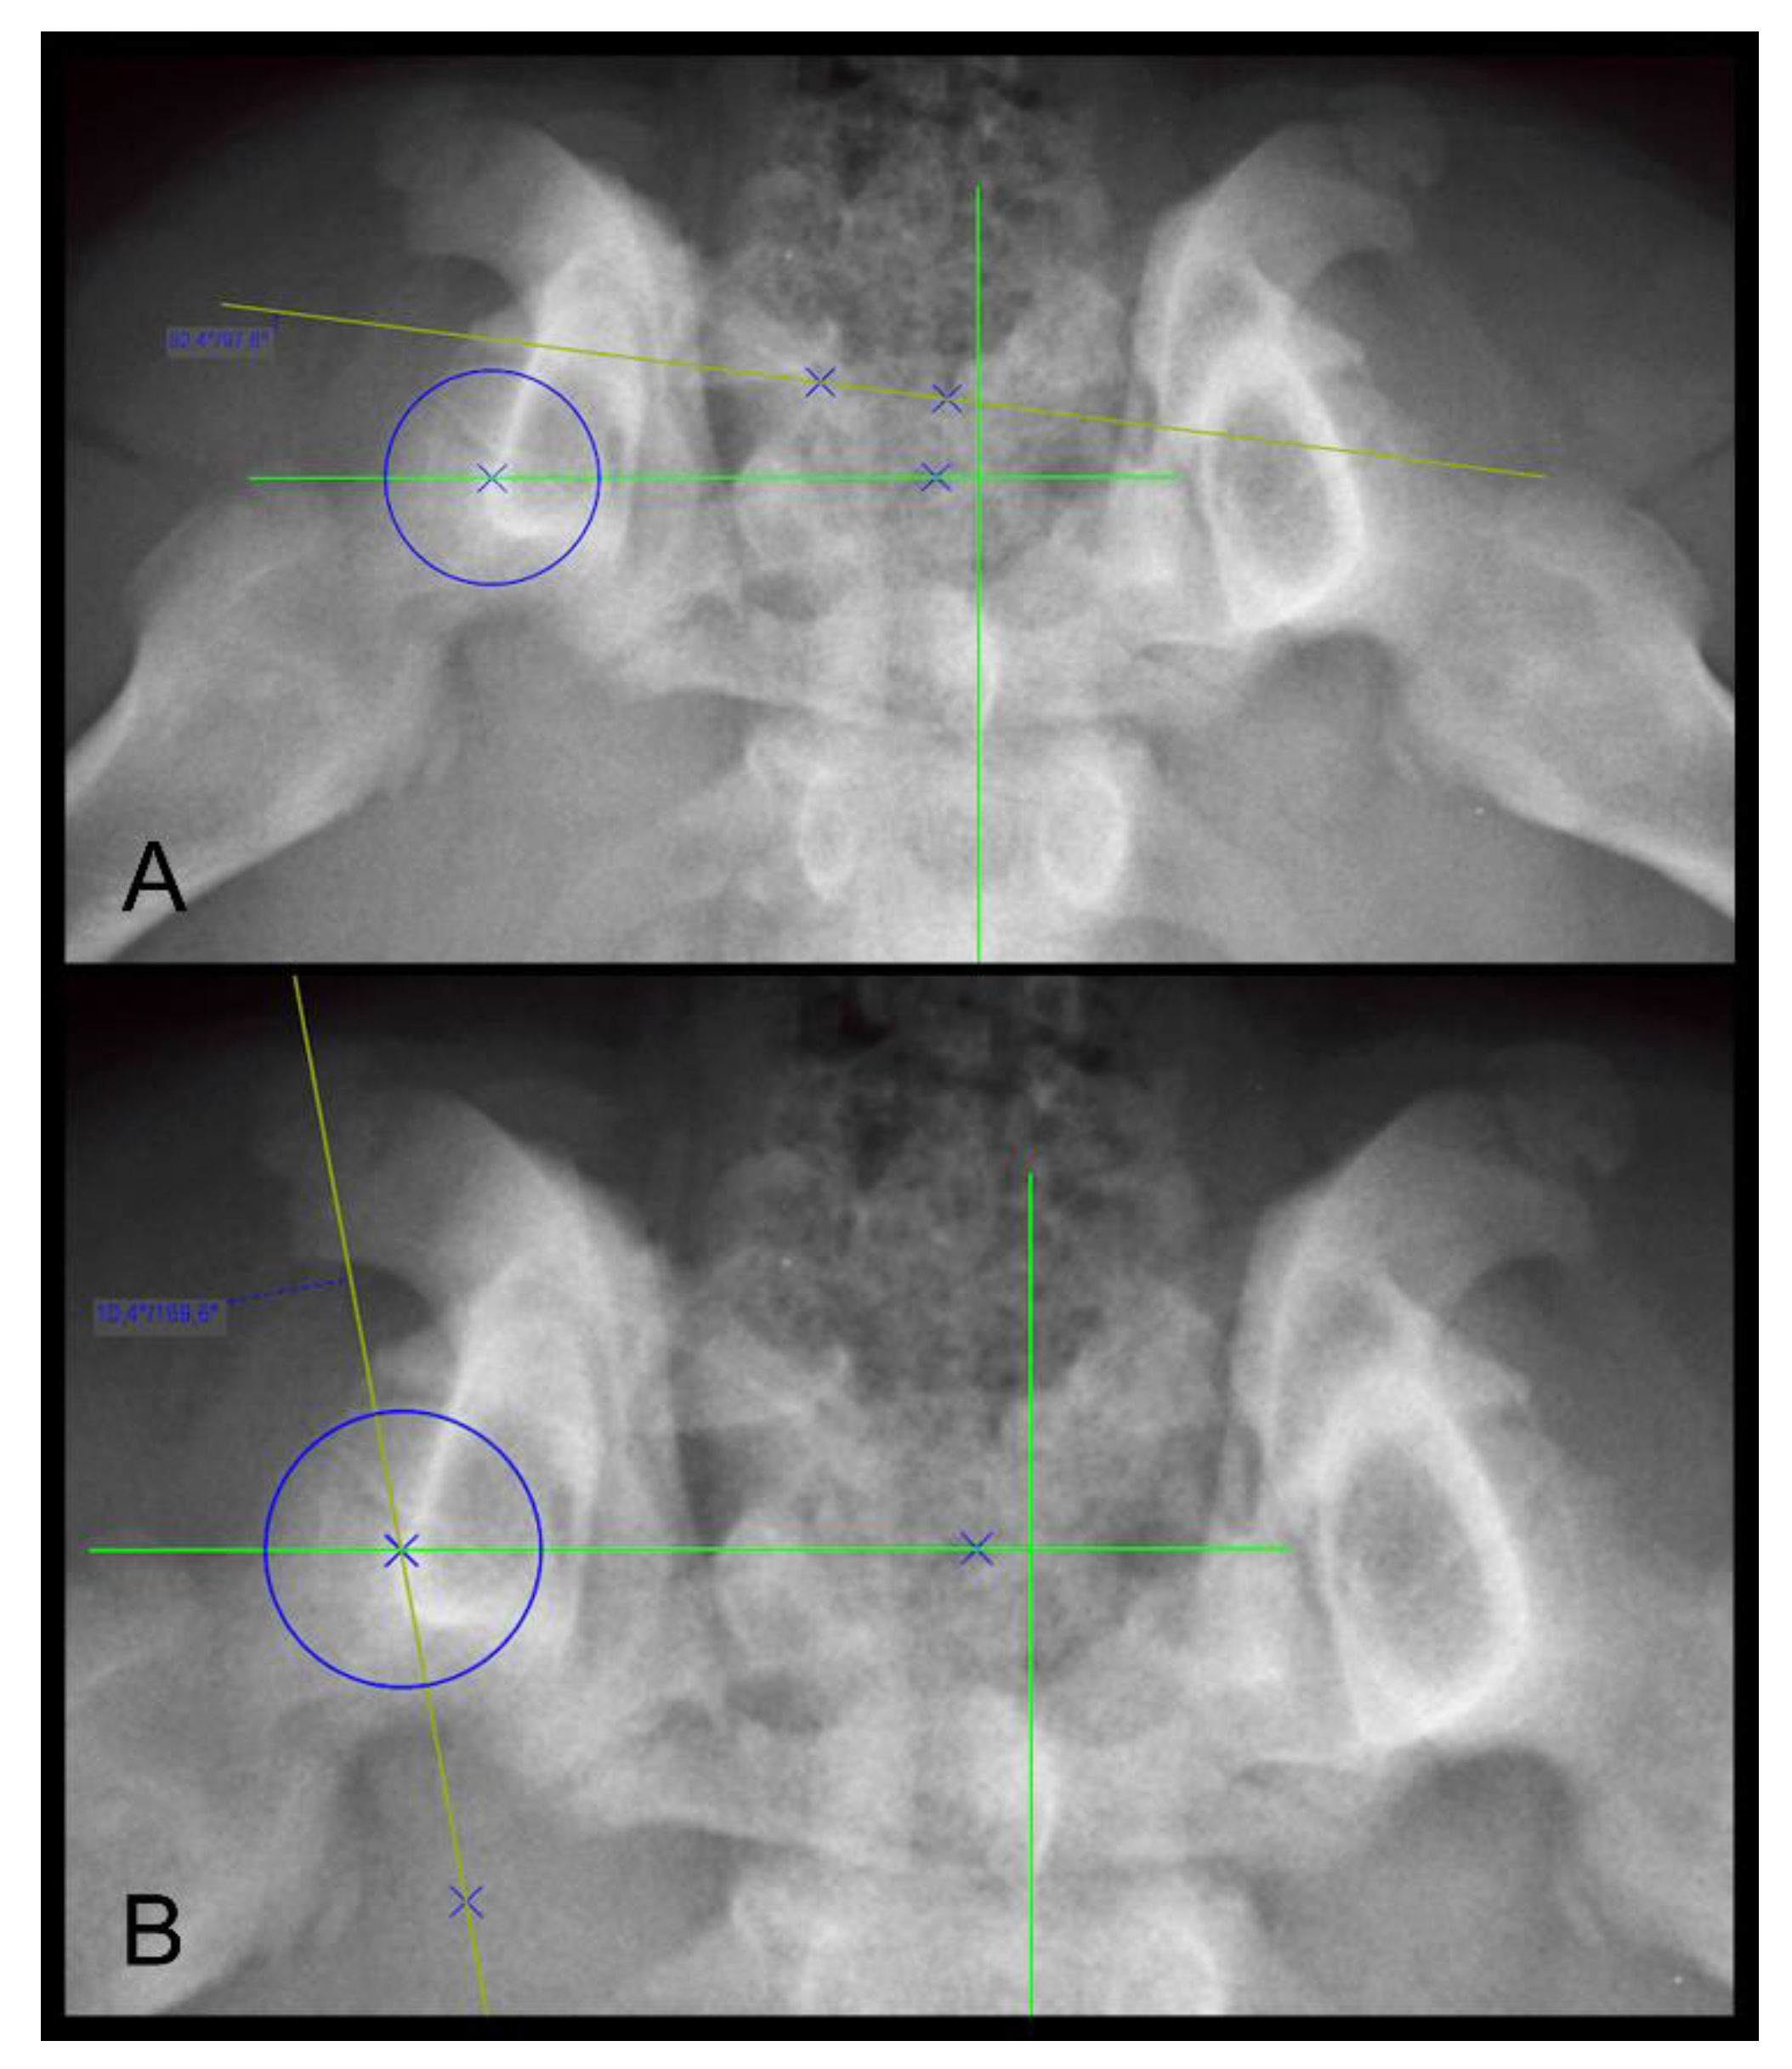

2.5.1. The Norberg Angle (NA)

The NA presents information about the location of the center of the femoral head relative to the craniolateral acetabular margin and is reported to be ≥105° in normal hips in most breeds [1]. Smaller NA values usually represent subluxated/luxated femoral heads. The measurement of the NA is based on the measurement of the angle between the straight line connecting the centers of the contralateral femoral heads in ventrodorsal radiographs and the line connecting the center of the femoral head at each side with the intersection of the dorsal rim and craniolateral border of the acetabulum. The measurement of the NA is shown in Figure 1.

2.5.3. Location of the Center of the Femoral Head (LCFH)

The LCFH was evaluated according to its position relative to the dorsal acetabular rim (medial, on, or lateral). The results were categorized as medial to DAR, superimposing DAR, 0–2 mm lateral to DAR, and more than 2 mm lateral to DAR (Figure 1).

Figure 1. (A) Extended FCI conform ventrodorsal radiograph of a four-month-old Rottweiler with what were assumed to be normal hip joints. Note the transitional lumbosacral vertebrae (type III). Right is always to the left of the images. (B) Magnification of (A), focusing on the hip joints: demonstration of Norberg angle measurement. (C) Section of a VD radiograph in another four-month-old Rottweiler puppy with obvious laxity of both hip joints, more severe on the left side. The femoral head center is positioned on, or barely medial to, the dorsal acetabular rim in (B) and definitely lateral to the DAR in (C) bilaterally. (D) Magnification of (C), demonstrating the actual distance of the femoral head center from the DAR.